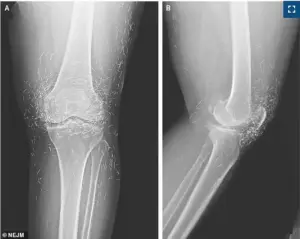

During an X-ray to assess her knee condition, doctors were stunned to discover hundreds of tiny gold threads embedded deep within her joints, a byproduct of a prior acupuncture treatment.

The X-ray revealed the threads clustered around her kneecaps, extending into her shin bone and upper thigh—a distribution that could interfere with future diagnostic imaging. ‘This is a textbook example of how alternative treatments can complicate medical care,’ said Dr.

Min-Young Park, a radiologist at Seoul National University Hospital, who reviewed the scans. ‘These threads were so numerous and diffuse that they obscured critical anatomical details, making it harder to assess the full extent of her osteoarthritis.’